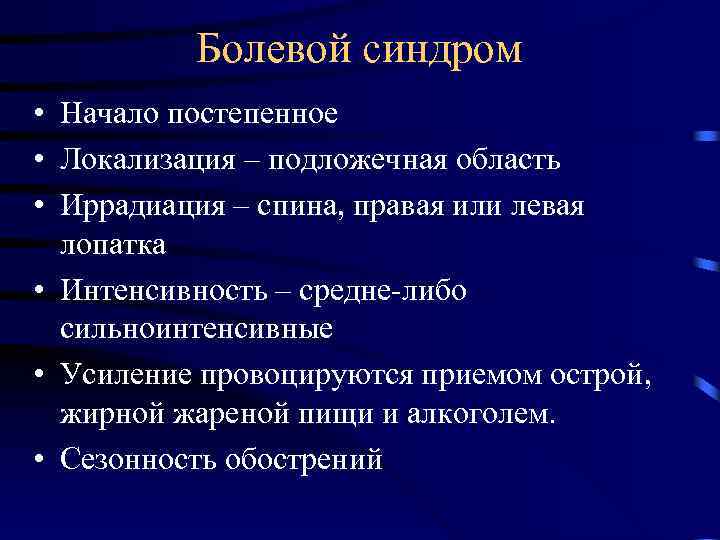

Болевой синдром • Начало постепенное • Локализация – подложечная область • Иррадиация – спина, правая или левая лопатка • Интенсивность – средне либо сильноинтенсивные • Усиление провоцируются приемом острой, жирной жареной пищи и алкоголем. • Сезонность обострений